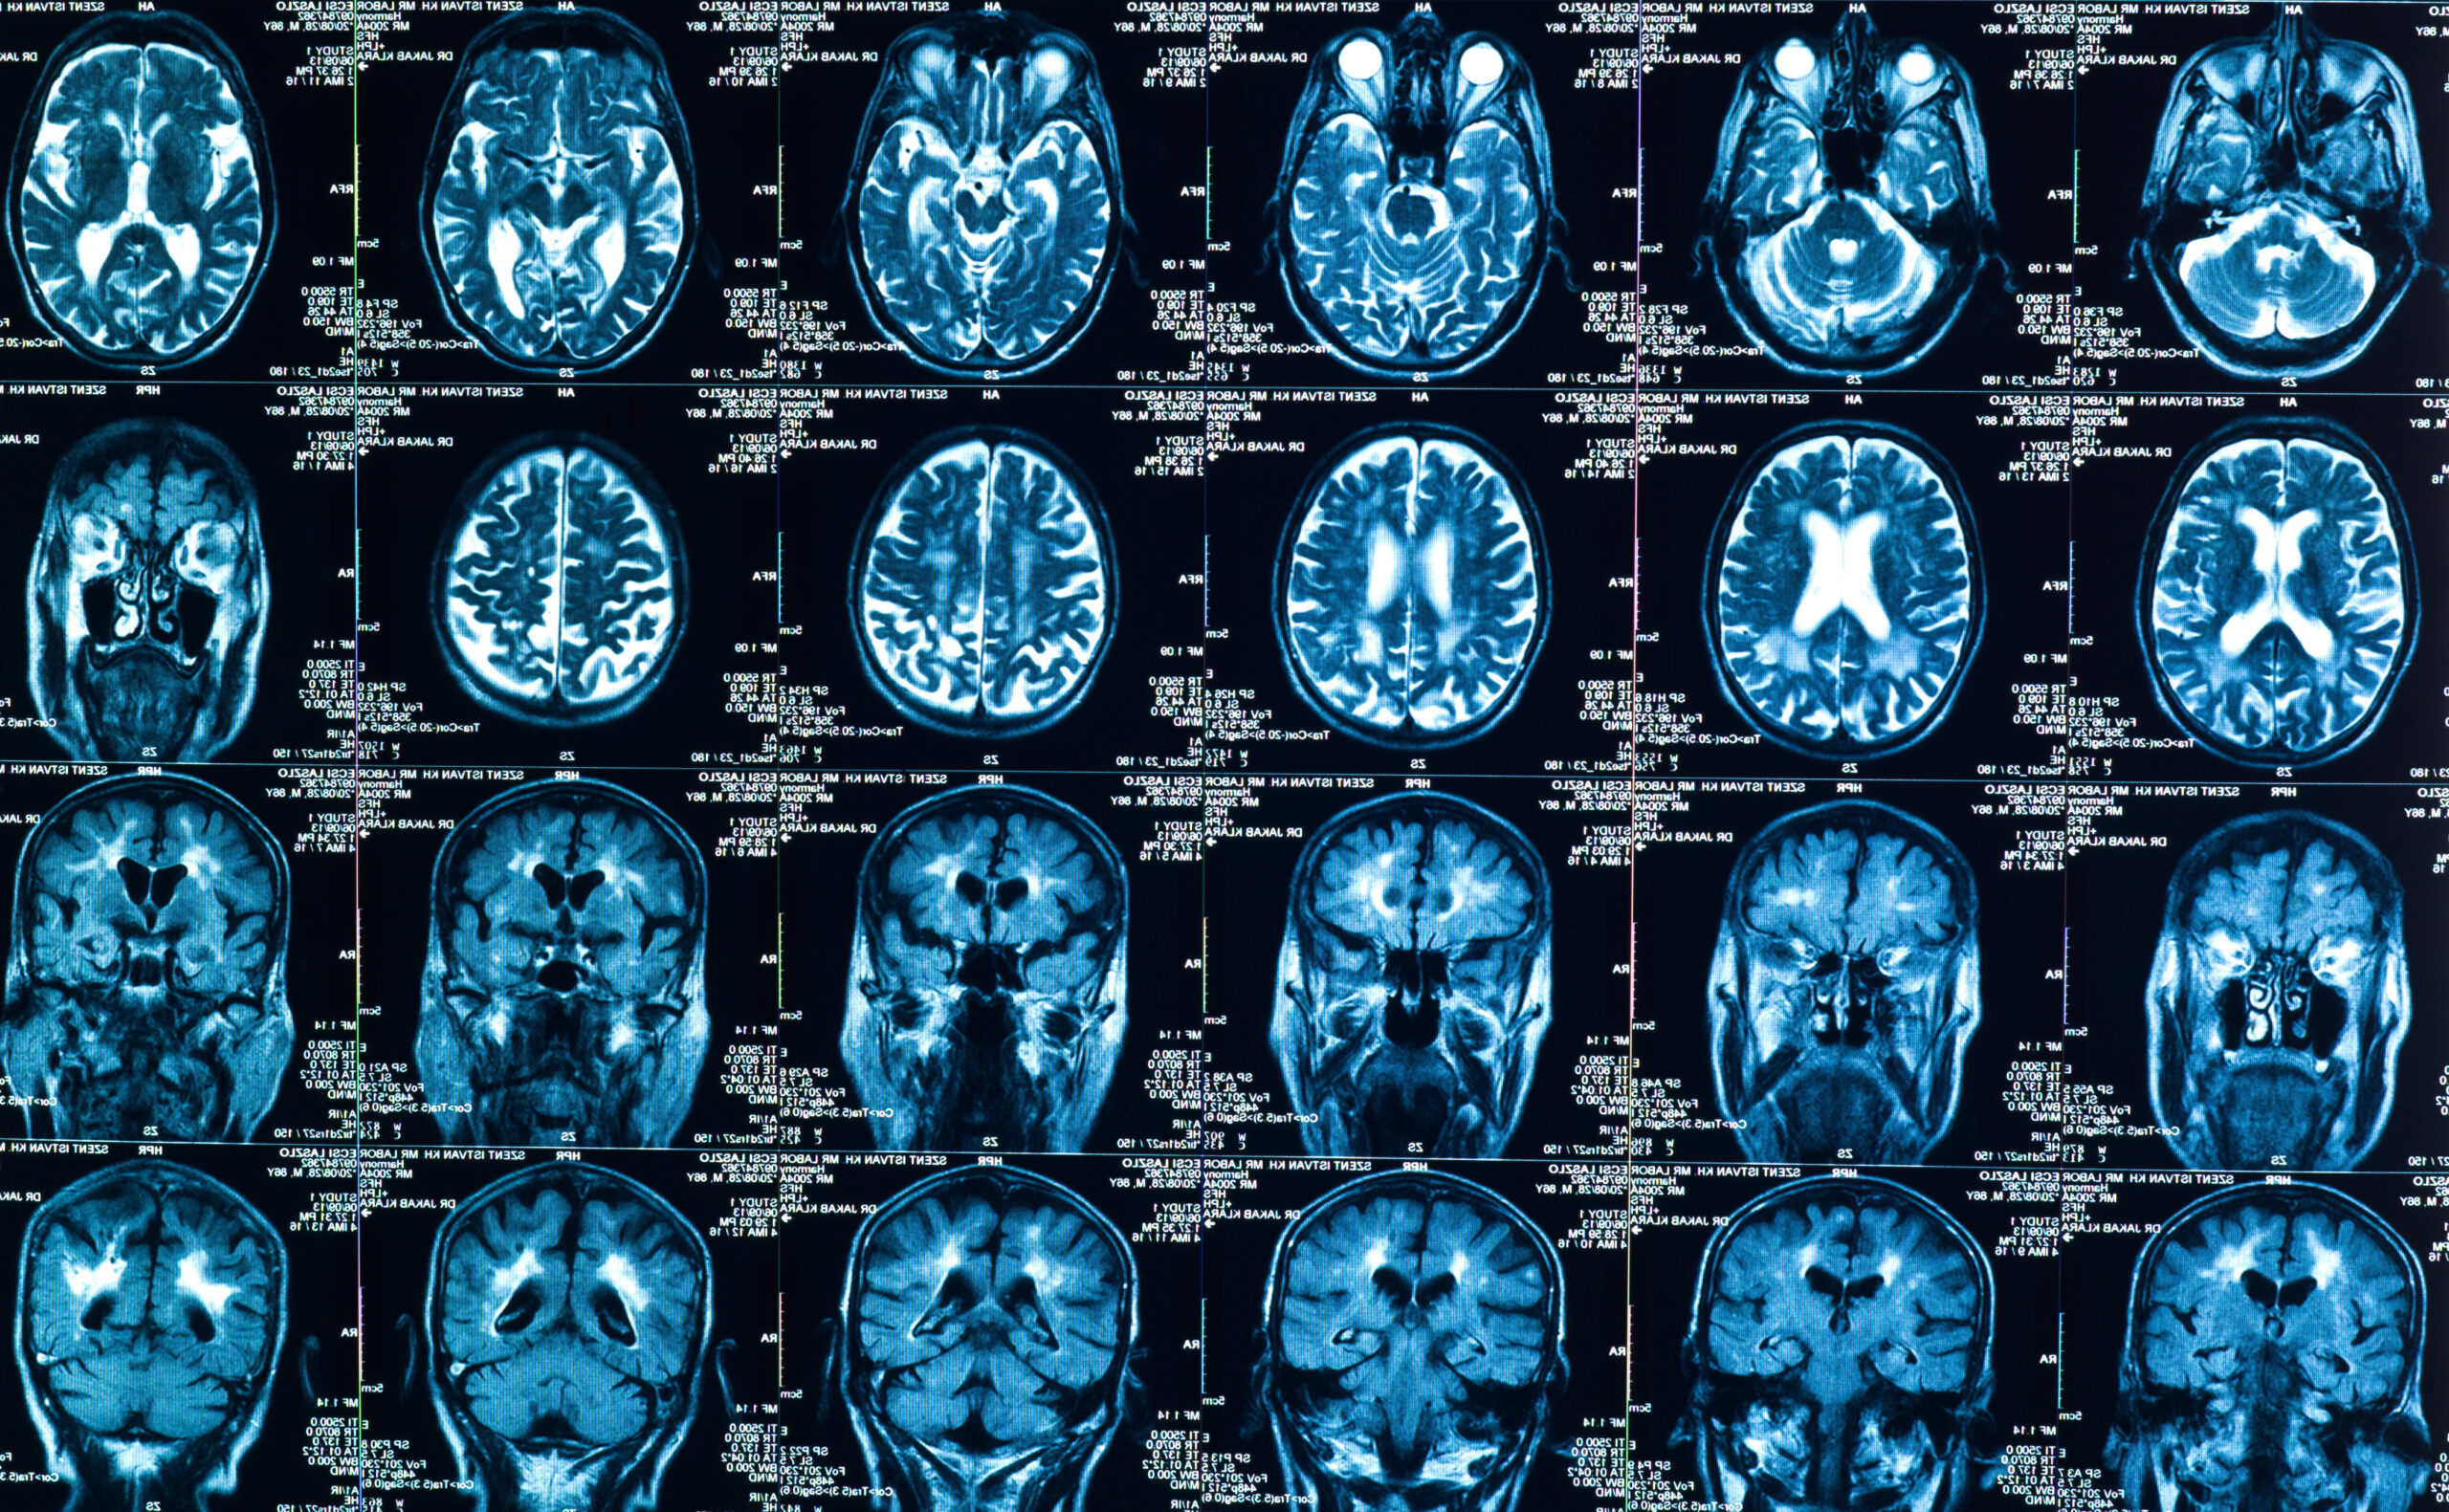

Most of the information about the progression of tumors in cancer patients is contained in written notes from radiologists, who examine scans and track changes in the status of the cancer. Because it’s raw text—not choices from a drop-down menu or data points in a spreadsheet—most analytic methods can’t pull the relevant information. The tool created in this study leveraged improvements in machine learning for language to identify those details in electronic health records.

For this particular tool, the scans from cancer patients were initially read by human radiologists. But artificial intelligence and machine learning can read images, as well, and research shows that they can analyze scans of tumors as effectively as human radiologists. In another study published this month, radiologists and artificial intelligence experts partnered to develop an algorithm that could determine if lumps on a thyroid should be biopsied—and found that recommendations from the machine learning tool recommended biopsies similarly to expert radiologists using the American College of Radiology (ACR) system.

Visual analysis is further along in medicine and oncology than textual analysis, Kehl says, but both could be components of integration of machine learning into the normal practice of care. It might be possible, for example, to integrate machine interpretation of scans into the overall electronic health record analysis, he says. “That would mean looking at how much information we get from images themselves, how much do we get from human interpretation, and what could we get from the model looking at images,” he says. “The optimal strategy still isn’t known.”